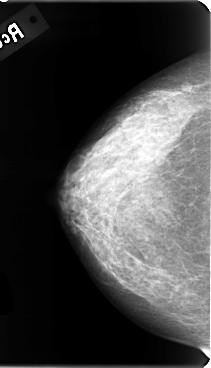

B_3085_1.RIGHT_MLO

RIGHT_CC LINES 4776 PIXELS_PER_LINE 2736 BITS_PER_PIXEL 12 RESOLUTION 50 NON_OVERLAY

RIGHT_MLO LINES 4784 PIXELS_PER_LINE 2920 BITS_PER_PIXEL 12 RESOLUTION 50 NON_OVERLAY